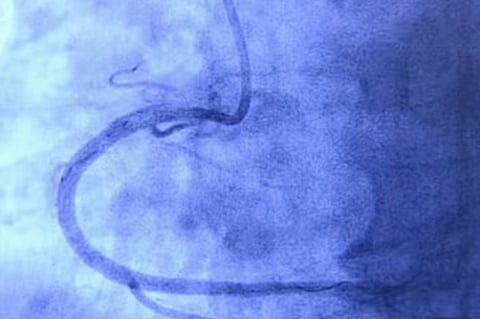

The technique is called Percutaneous Coronary Intervention (PCI), where the cardiologist will make a small opening in the hand of the patient, and insert a catheter (wires and tubes) into the a primary artery, and will approach the blocks near the heart. Once there, the doctor will blow a balloon up to push the blocks away and out of the path of the blood flow. Once Dr. YVC is satisfied that the heart is beating normally and blood flow is perfect, he will remove the catheter, and close the opening in the hand. This form of angioplasty - called the Trans Radial Angioplasty - was pioneered in India by Dr. YVC

In certain cases, the doctor may also implant a stent which holds the artery wall up, pushes the plaque against the wall, and ensures blood flow is free.